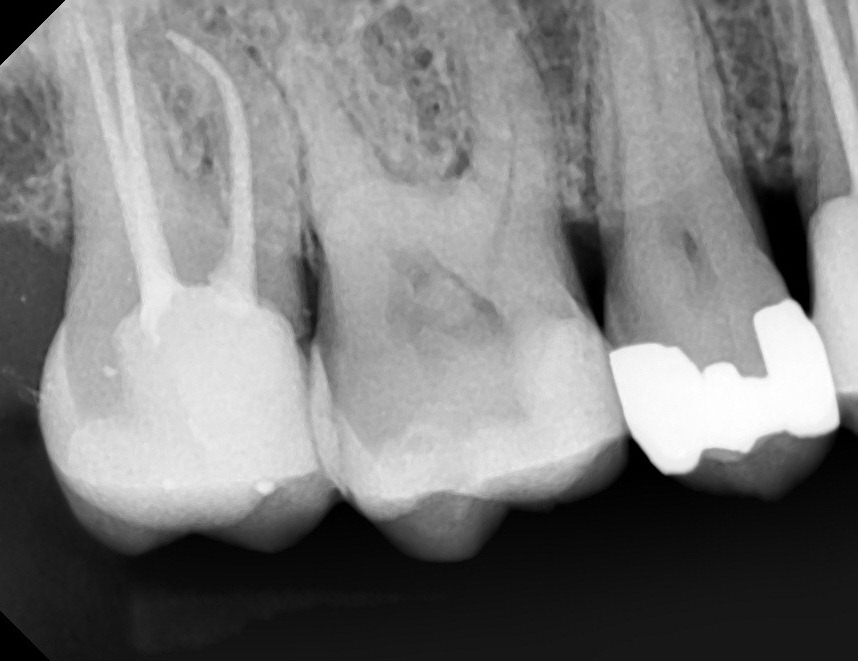

- Role of a pre-operative radiograph

- Surgical & Non-surgical treatment protocols for Periapical cyst / radiolucency

- CASE DISCUSSION & ESTABLISHING DIAGNOSIS WITH RADIOGRAPHS